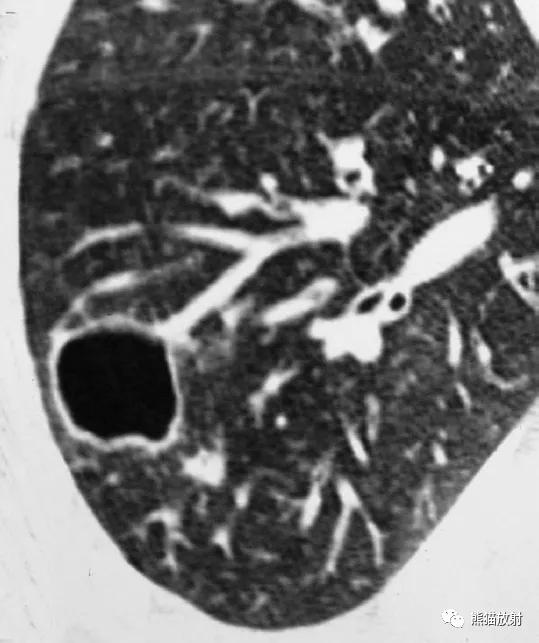

↑ 肺脓肿 Lung abscess

35岁男性,高热,大量浓痰。痰培养铜绿假单胞菌阳性。CT示左肺上叶的大空洞,空洞内见粗大分隔。